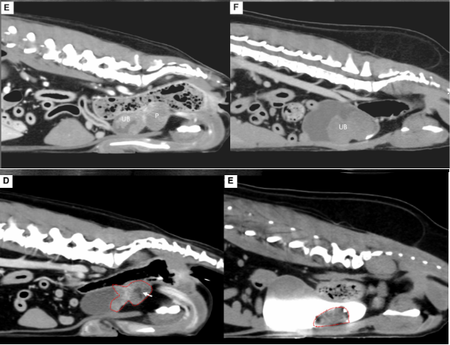

■ 방광 종양으로 인한 빈혈 환자에 ‘방광 종양 색전술’ 성공

첫 번째 논문은 거대 방광 종양으로 지속적인 혈뇨와 빈혈을 보인 개 2마리에서 종양 색전술을 적용한 사례로 'Journal of Small Animal Practice(SCI)'에 게재됐다.

전통적으로 비뇨기 종양 색전술은 합병증 위험으로 전립선 종양에만 국한됐지만 본 증례는 종양으로 공급되는 혈관만을 초선택(superselective) 했고, 시간이 지나 재개통이 되는 색전 물질(gelatin sponge particle)을 이용해 효과를 극대화 하면서도 심각한 합병증이 발생하지 않도록 하였다.

시술 직후 혈뇨는 즉시 개선됐으며, 배뇨곤란 증상도 완화됐다. 또한 종양 크기는 50% 이상 감소했으며, 빈혈과 혈소판 감소증을 보였던 환자에서도 4주만에 혈액 수치가 정상화 되었다.

해마루 인터벤션센터는 현재까지 하부 비뇨기 종양 색전술을 200례 이상 시행했으며, 30여 마리를 장기 추적한 전향적 연구도 유명 SCI 저널 게재를 앞두고 있다.